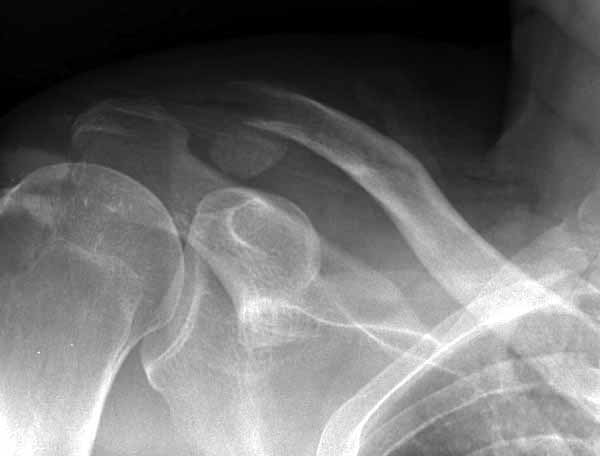

Дальше - «методики применения ключичной пластины с крючком при акромиальных переломах”, т. е не ведется разговор “по поводу лечения косых переломов ключицы”. - А разве акромиальный перелом ключицы не может быть косым???

Потом, к сожалению и Юрий, и Вы ошиблись в не существовании такой методики. Открываем AO Principles of Fracture Management\2007\ стр.567-568. Есть еще на сайте АО-травмы Lateral Clavicle≈Dislocations and Fractures≈The LCP Clavicle Hook Plate . Там акцент методики применения ключичной пластинки с крючком именно и при вывихах, и при переломах!!!

Я ставил польскую http://www.chm.pl/pliki/9878cd2387f303265ebad595b2519dce.pdf, но у них еще не опубликована методика

Но это не помешало успешно пациента прооперировать.